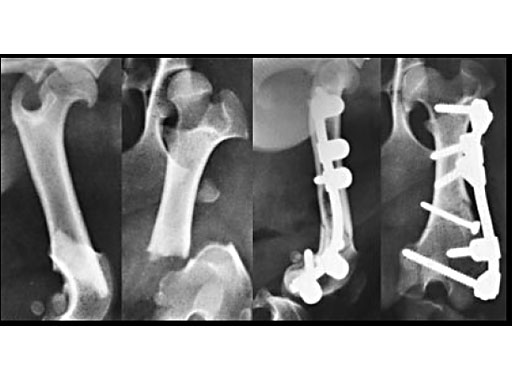

Clinical application in small animals: A 1-year-old female Dachshund was admitted with a transverse fracture in the distal metaphysis of the femur. Fixation was accomplished with a 2 mm interfragmentary screw in a lag fashion and a 2.7 mm VetFix with five screws. The fracture healed and the implants were removed four months postoperatively. The benefit of the VetFix can be shown on this breed of dog, the females of which do not have one straight bone in their body. The rod was contoured along the bone, which is not possible with a plate.

1-year-old Dachshund

(Case provided by K. Zahn and U. Matis, Munich, Germany)